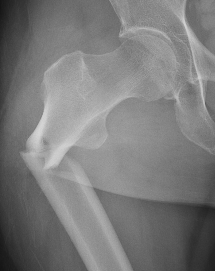

Definition

Fracture below lesser trochanter

Proximal 5 cm femoral shaft

1. Proximal fragment flexed, in varus and externally rotated with distal fragment adducted

- iliopsoas flexes proximal fragment

- abductors cause varus of proximal fragment

- external rotators rotate proximal fragment

- adductors medialize distal fragment